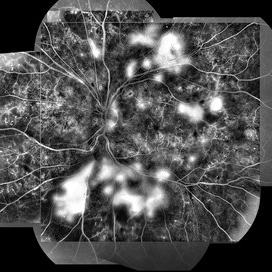

Syphilis Neuroretinopathy

Female patient, 21-years-old, with complaint of low vision in the right eye for 3 years. According to information from the patient's history, at the time she noticed the low vision, it also coincided with a picture of a strong urinary infection as well as episodes of constant tonsillitis. Yes, the patient did not seek medical attention and self-medicated with antibiotics. In ophthalmologic evaluation, as well as examinations of color retinography and ocular fundus autofluorescence, important pigmentary alterations were observed following vascular arches with pigment mobilization in osteoclasts (aspect of a unilateral pigmentary retinitis secondary to the inflammatory process). Which suggested inflammatory process sequelae. Through the laboratory tests, he had positive (+) confirmation for SYPHILIS NEURORETINOPATHY .

Photographer: JEFFERSON R SOUSA - Study Center and Ophthalmological Research Dr. Andre M V Gomes, Institute Dr. Suel Abujamra São Paulo-Brazil

Imaging device: Fundus camera Topcon TRC-50 DX, Imaginet 5.0, angle de 50 graus. Flash 36 / Mosaic with 10 images.

Condition/keywords: neurosyphilitic optic atrophy, retinitis pigmentosa, syphilis, syphilis neuroretinopathy